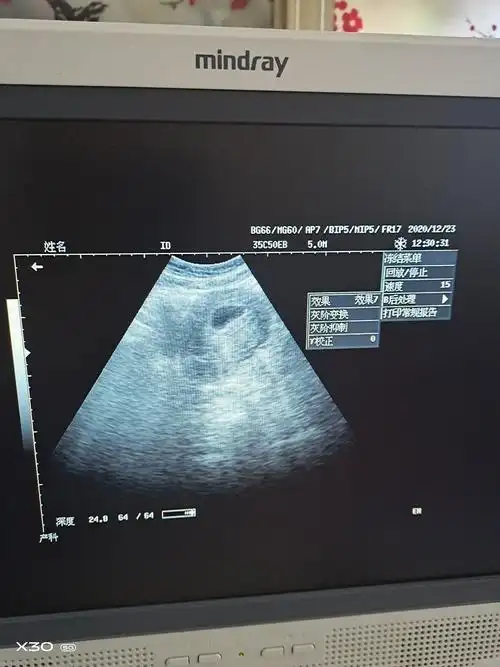

有会看孕囊的吗